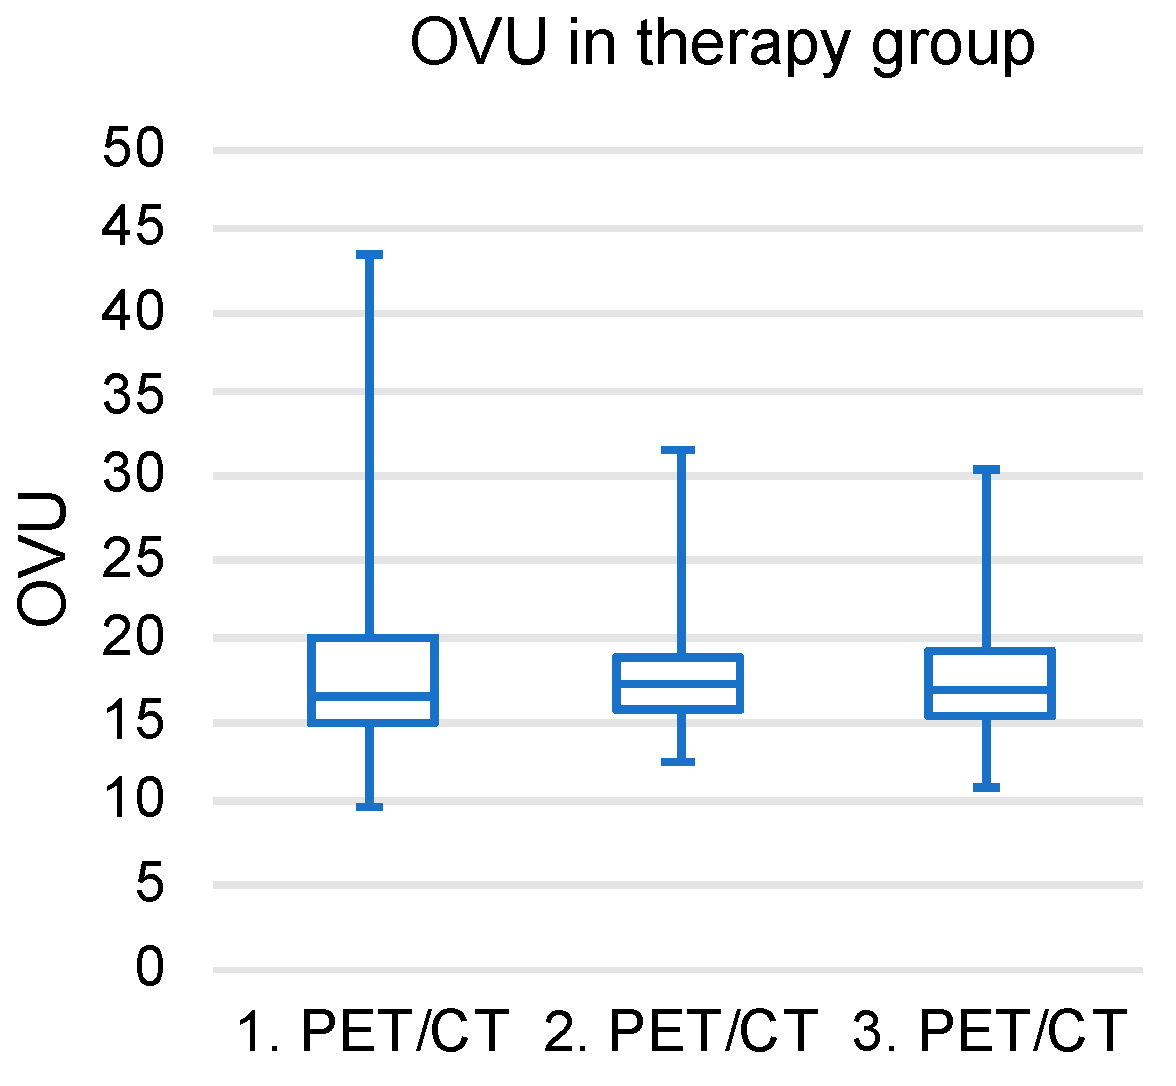

3.4. Longitudinal OVU Evaluation in the Therapy Group

3.5. Tercile-Based Analysis of Patient Cohorts